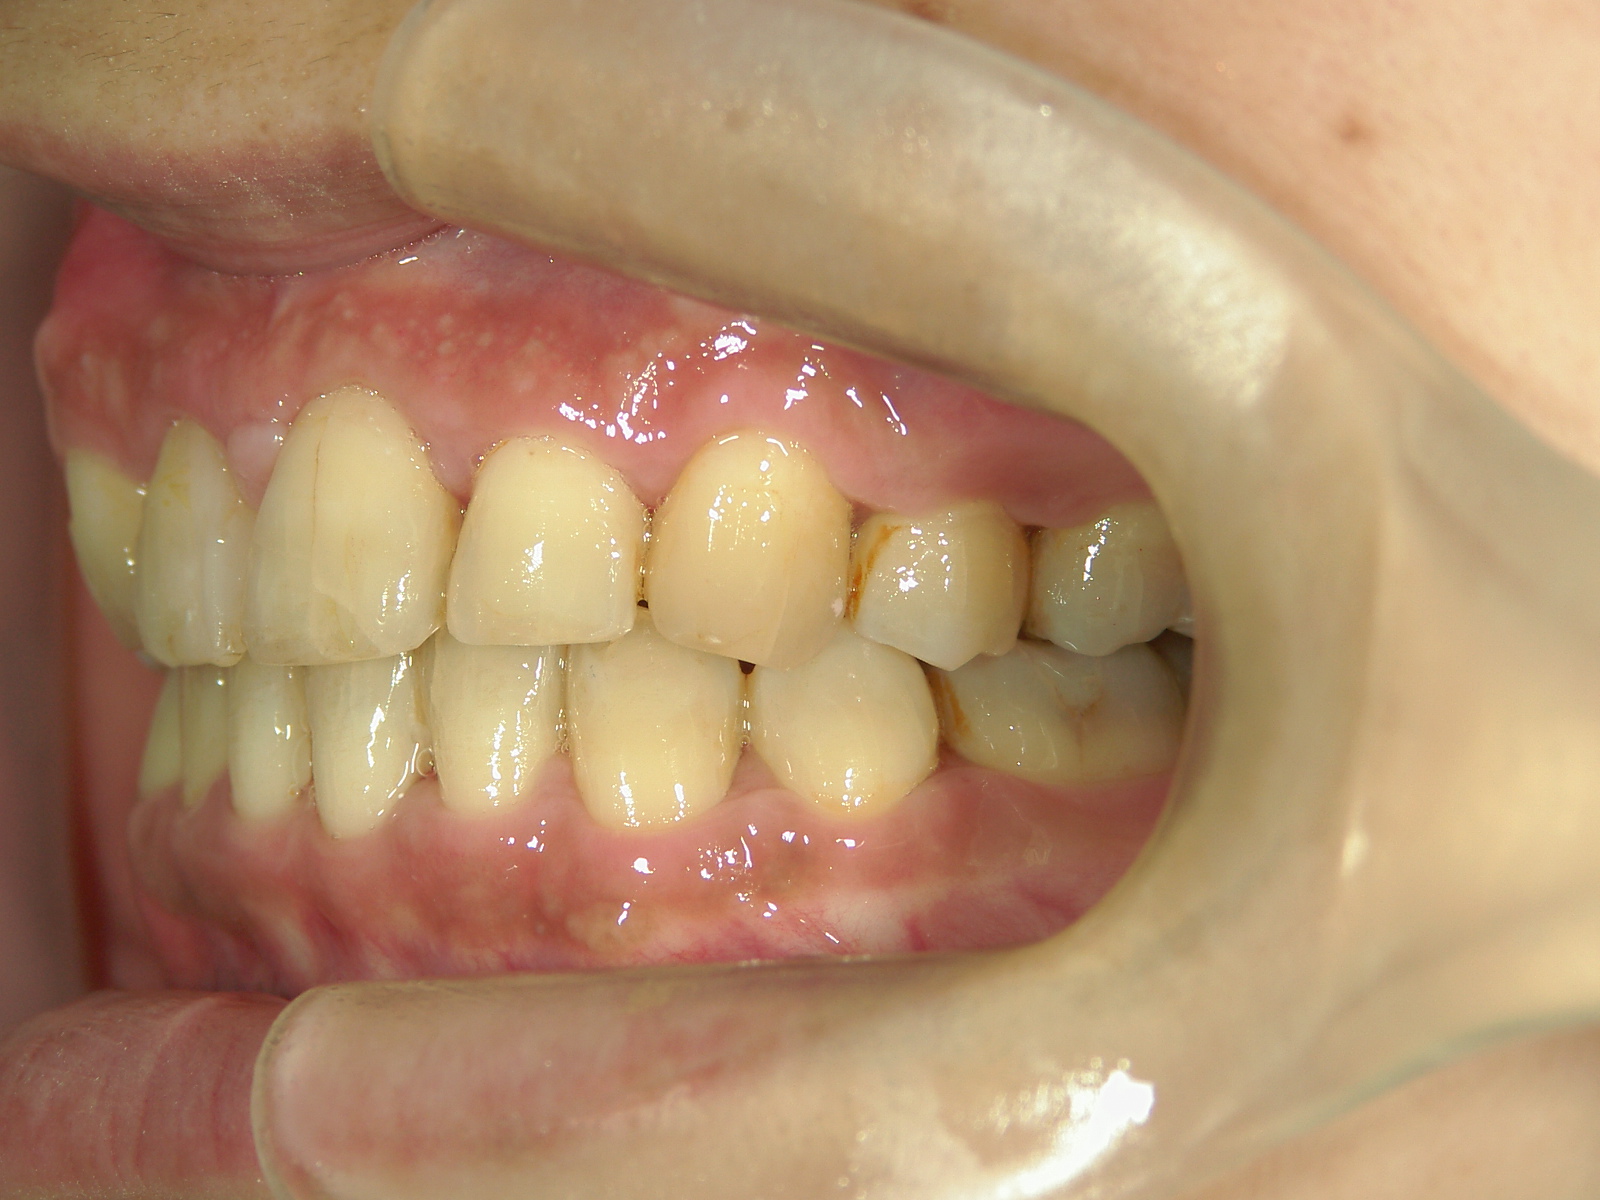

主訴: 8年前の事故でぶつけて歯根吸収していた為、前突・叢生が気になる。

右上中切歯 抜歯後、空隙を閉鎖しました。

歯根の移動後、元々の中切歯の形に硬質レジンで歯冠を形態修正しました。

左右下 第一小臼歯2本、左上 第一大臼歯1本、右上 前歯1本を抜歯。

・抜歯した右上前歯の隣りの歯を抜歯してあいたスペースで移動。

・右上犬歯を移動して、開いたスペースへ移動。

・右上 第一小臼歯を移動して犬歯のスペースへ移動。